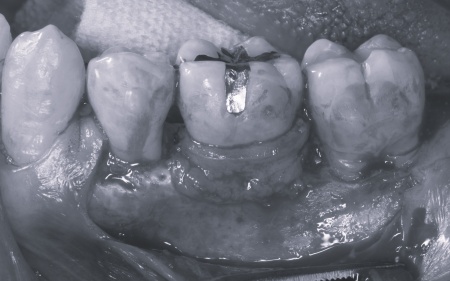

| カウンセリング | 拝見したところ、上下の歯は、ずれたりねじれたりしてデコボコに生えており、著しく歯並びが乱れていました。

またレントゲン撮影をして確認すると、右上前歯は顎の骨の中に埋まっている骨性埋伏(こっせいまいふく)の状態でした。 さらに、左下奥歯は重度の歯周病であり、歯を支えている骨が一部溶けていることが判明しました。 以上のことから、歯並びを整える矯正治療と歯周病の治療を併せて行う必要があると診断しました。 |